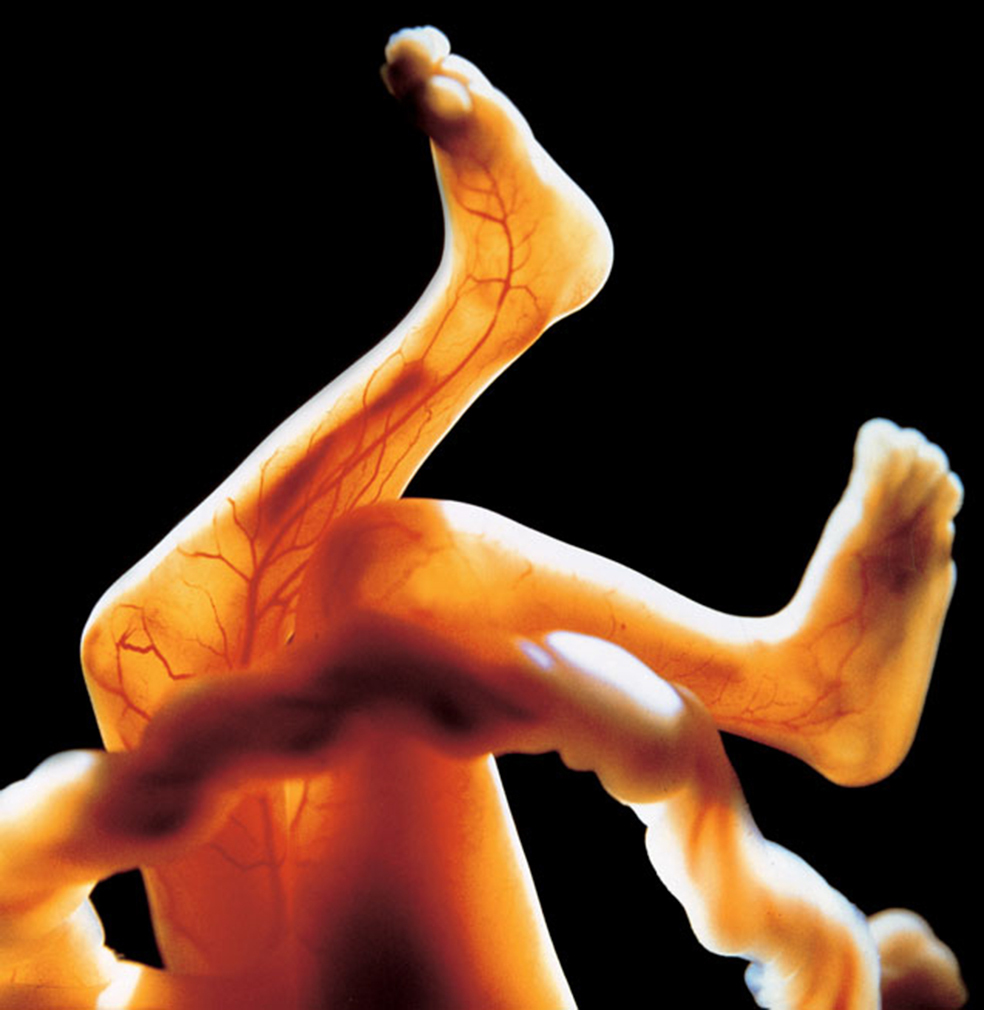

El espejo del alma

El embrión continúa creciendo y definiendo sus características. A partir del quinto mes, el pelo ya tiene un color visible. El proceso de calcificación en los huesos de las piernas y de los brazos ha comenzado.

Un cuerpo 16

A los cuatro meses, el cuerpo está cubierto de pelo fino llamado lanugo. El cordón umbilical se une al abdomen. El feto, del tamaño del puño de su madre, bebe líquido anmiótico y orina. A partir del quinto mes, ya se chupa el dedo y hasta tiene hipo.